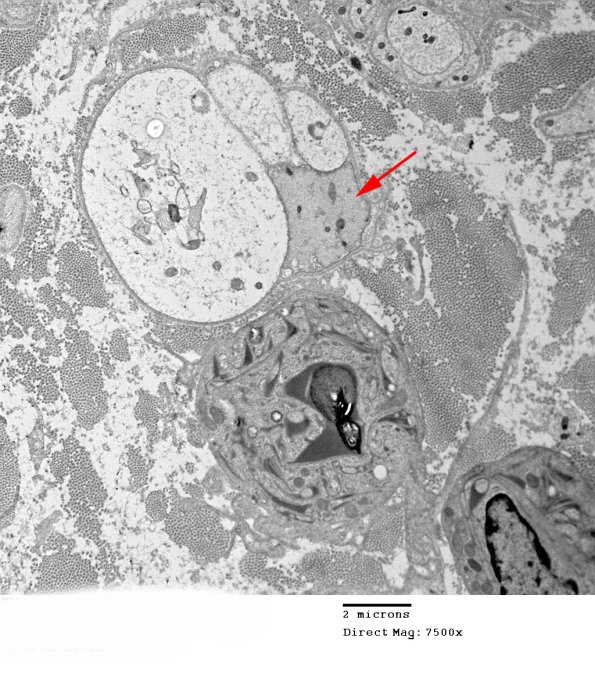

The completion of the demyelinating process results in naked axons (arrows) which may be difficult to separate from adjacent Schwann cell processes at low magnifications. (electron micrographs)